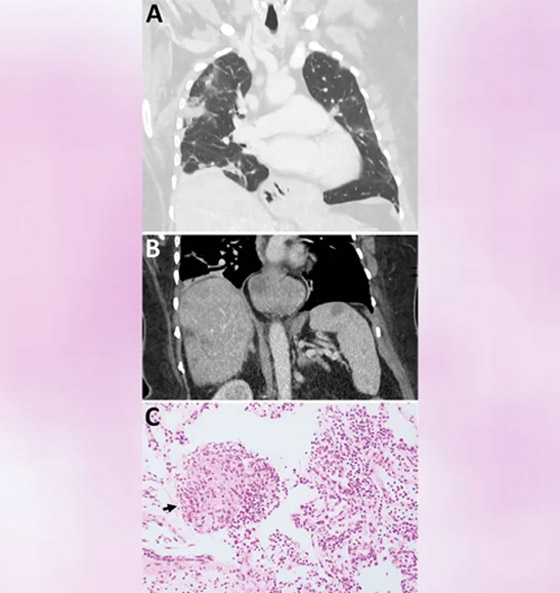

في حادثة طبية مدهشة، اكتشف أطباء في مستشفى كانبيرا في أستراليا دودة حية في دماغ امرأة تبلغ من العمر 64 عاماً. وتمكنت الدكتورة هاري بريا باندي جراحة الأعصاب من سحب الدودة التي يبلغ طولها 8 سنتيمترات من المريضة.

وأدخلت المريضة، مستشفى محلي في نيوز ساوث وليز في أواخر يناير 2021 بسبب آلام في البطن وإسهال وسعال جاف مستمر وحمى وتعرق ليلي. وتفاقمت الأعراض في 2022 لتشمل النسيان والاكتئاب. ثم أدخلت مستشفى كانبيرا، حيث كشفت فحوص الرنين المغناطيسي لدماغها عن وجود تشوهات تتطلب عملية جراحية. لتجري هاري بريا، الجراحة وتكتشف وجود هذه الدودة الحية.